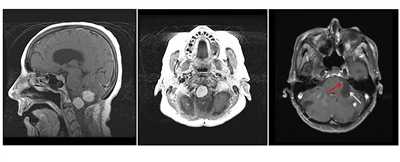

Hemangioblastomas de cerebelo y médula espinal

Los hemangioblastomas son la manifestación más común en los pacientes con enfermedad de VHL y afectan a más del 70 % de las personas. En un estudio prospectivo se evaluó la evolución natural del los hemangioblastomas.[16] La media de edad de aparición de los hemangioblastomas del sistema nervioso central (SNC) es de 29,1 años (intervalo, 7–73 años).[17] Los hemangioblastomas del SNC se observaron con mayor frecuencia en el cerebelo (45 %), la médula espinal (36 %), la cola de caballo (11 %) y el tronco encefálico (7 %).[18] Aunque los hemangioblastomas esporádicos son casi siempre solitarios por naturaleza, las lesiones en el SNC asociadas a la enfermedad de VHL a menudo son multifocales. Luego de una media de seguimiento de 7 años, el 72 % de 225 pacientes estudiados presentaron lesiones nuevas.[18] En las figuras 2 y 3 se muestran hemangioblastomas de cerebelo y médula espinal, respectivamente, en pacientes con enfermedad de VHL.

En la imagen se observan tres paneles. En el panel de la izquierda se muestra una vista sagital de dos lesiones prominentes de color claro en el tronco encefálico y el cerebelo. En el panel del medio se muestra una vista axial de una lesión prominente en el tronco encefálico. En el panel de la derecha se muestra una vista axial de una lesión en el cerebelo con un componente quístico que se ve como un área grande y oscura.

Vista sagital del cuello donde se observan varias lesiones de color claro en la médula espinal.